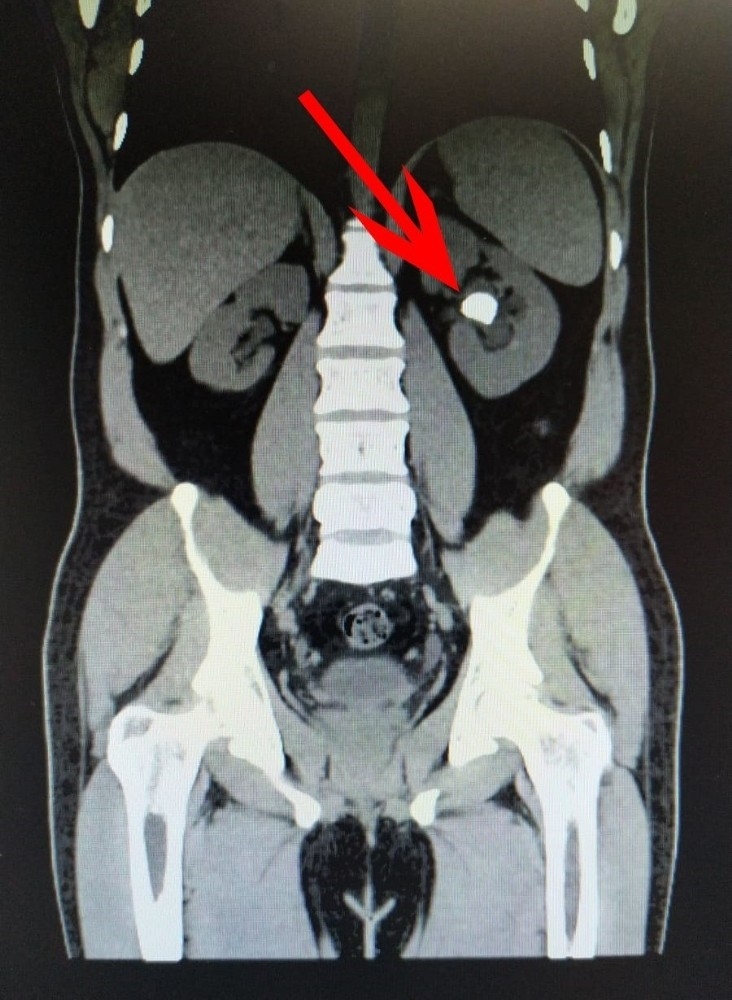

Manisa Şehir Hastanesinde çalışan Hanifi Tekin, yaklaşık 4 yıldan bu yana çektiği böbrek ağrıları sebebiyle görev yaptığı hastanenin Üroloji Kliniğine başvurdu. Üroloji Uzmanı Dr. Volkan Tatlı tarafından tetkikleri yapılan Tekin'in sol böbreğinde 22 milimetre taş olduğu tespit edildi. Genç yaşı ve çalışan bir hasta olması sebebiyle ESWL (taş kırma) işlemi uygun görülmeyen hastaya kapalı taş ameliyatı planlandı. Ameliyata alınan Tekin'in sırtından bir tüp ile böbreğine bir kanal açılarak, taşları kırılıp boşaltma işlemi gerçekleştirildi. Başarıyla tamamlanan ameliyat sonrası Hanifi Tekin, sağlığına kavuştu. Başarılı ameliyatı yapan Üroloji Uzmanı Dr. Volkan Tatlı, "Hastamız Hanifi Tekin 28 yaşında ve hastane çalışanımız aynı zamanda. Böbrek ağrısıyla kliniğimize başvurdu. Yapılan tetkikler sonunda sol böbreğinde 22 mm taş olduğu görüldü. Genç ve çalışan hasta olması sebebiyle ESWL işlemi uygun görülmedi. Kendisine Perkütan taş ameliyatı planlandı. Ameliyatını iki kez ertelemek zorunda kaldık. İlk defasında enfeksiyondan dolayı, ikincisinde tansiyon yüksekliğinden dolayı iptal oldu. Tansiyon yüksekliği nedeniyle Kardiyoloji konsültasyonu istendi. Değerlendirilerek tansiyon ilacı başlandı. Tansiyonları normale dönünce ameliyatını gerçekleştirdik. Yaptığımız ameliyat hastanın sırtından bir tüp ile böbreğe bir kanal açtık. Taşları kırıp boşaltma işlemini gerçekleştirdik. Bugün ameliyattan sonra birinci günü sondasını çıkardık. Yarında sırtında bulunan dreni aldıktan sonra genel durumu ile değerlendirilip post-op üçüncü günü hastamız taburcu edilecektir" dedi.